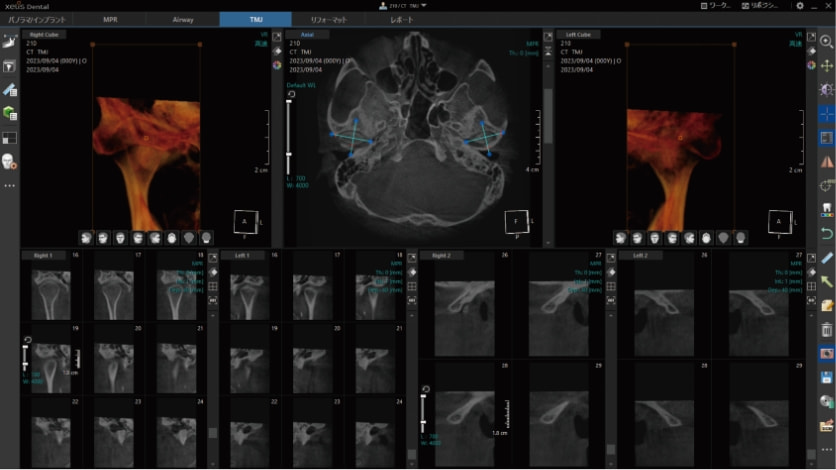

TMJ撮影

TMJ4分割撮影が可能です。

CT画像専用ビューアーソフト「 XelisDental(ゼリスデンタル )」

Pano/Implant、MPR、TMJの各種解析ツールをタブで切替できます。

タブの切替のみで、ツールアイコンが変化する為、迷わず操作が可能です。

VOI , Cube機能 / VRのスカルプト機能

MPR表示では、局所拡大表示も可能。

軸の回転に加え、スライス厚の変更やボリュームレンダリング画像のスカルプト機能も搭載。

VOIやCube機能で、解析部位を絞り込んで表示する事ができます。

TMJの左右同時検出

左右どちらかの下顎頭を指定すると、反対側の下顎頭を自動的に検出します。